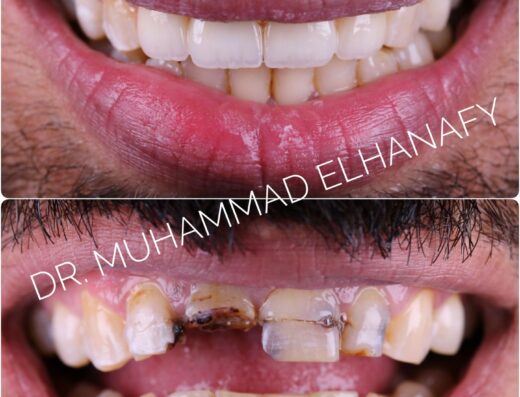

تحسين شكل الابتسامة بيعتبر خطوة مهمة في تجهيز العروسة أو العريس، وده بيخلي اختيار دكتور أسنان مناسب حاجة أساسية قبل المناسبة.

- تحسين شكل الابتسامة